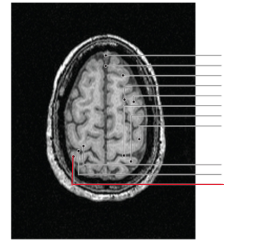

fissura longitudinalis cerebri

nucleus caudatus

putamen

globus pallidus

capsula interna (corona radiata)

capsula externa

hippocampus

amygdala

laterale ventrikels (I en II)